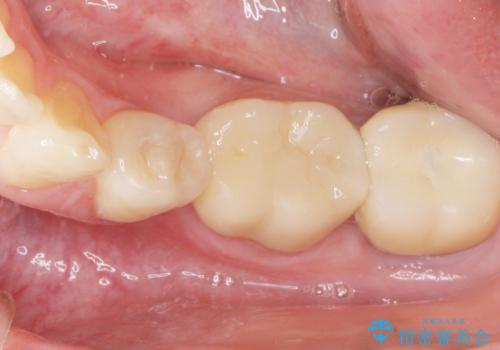

矯正は絶対にしたくないという強いご希望により、舌側転位している歯を抜去し歯肉の治癒を待ったのち、両隣の歯の補綴治療を行いました。

セラミッククラウンにより、抜歯した部分のスペースを閉じ歯並びを整えました。

矯正装置を用いることなくセラミッククラウンにより歯並びを整えスペースを閉じることができ、大変ご満足頂けました。